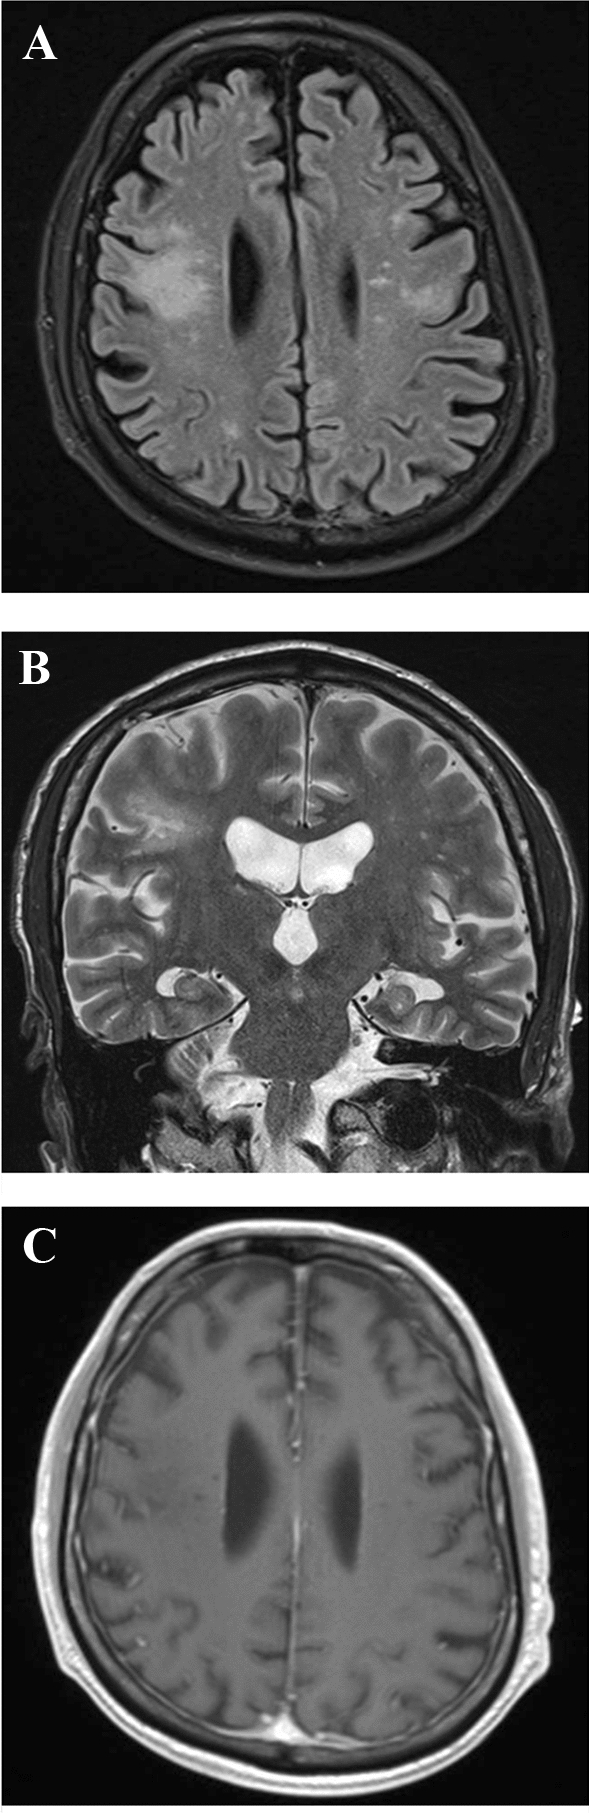

Blood tests showed severe lymphocytopenia (77/mm3). Brain magnetic resonance imaging displayed T1-hypointense, T2-hyperintense abnormalities of the frontal subcortical white matter, also involving the U-fibers and the frontal operculum bilaterally (mainly on the right side). No mass effect or contrast enhancement after gadolinium administration was evident (Fig. 1). On both T1- and T2-weighted sequences, the Milky Way sign was also observed (i.e., multiple point-like alterations surrounding the main lesions) (Fig. 1). Magnetic resonance spectroscopy (at intermediate echo time of 135 ms) of the right opercular lesion showed increased choline and decreased N-acetyl aspartate levels, and a lactate peak, indicating the presence of neuronal loss, necrosis and increased cell turnover. Cerebrospinal fluid (CSF) analysis showed a normal cell count, normal albumin quotient, and absence of oligoclonal banding, but the polymerase chain reaction was positive for JC virus DNA (390 copies/mL).

Fig. 1

Brain magnetic resonance imaging of the patient. Bilateral hyperintense alterations of the subcortical white matter of the frontal operculum, mostly on the right side, on axial FLAIR (a) and coronal T2-weighted sequences (b). The lesions are hypointense and do not show contrast enhancement on axial T1-weighted sequences (c). The Milky Way sign is evident on both T1- and T2-weighted sequences